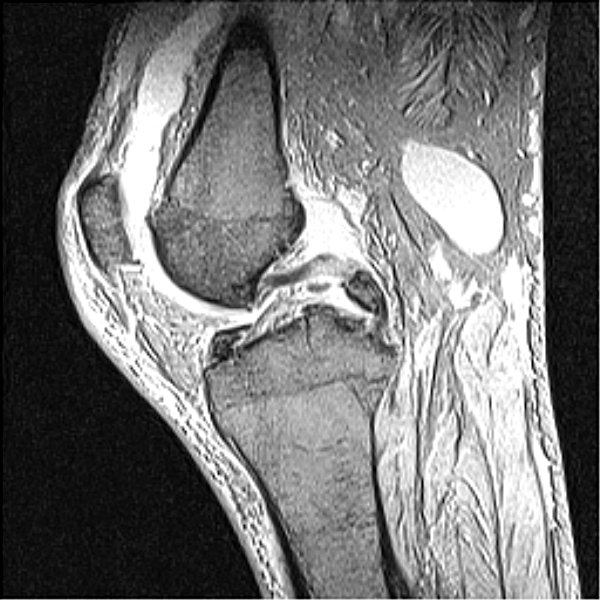

Return to Tibial Fracture (PCL Avulsion)